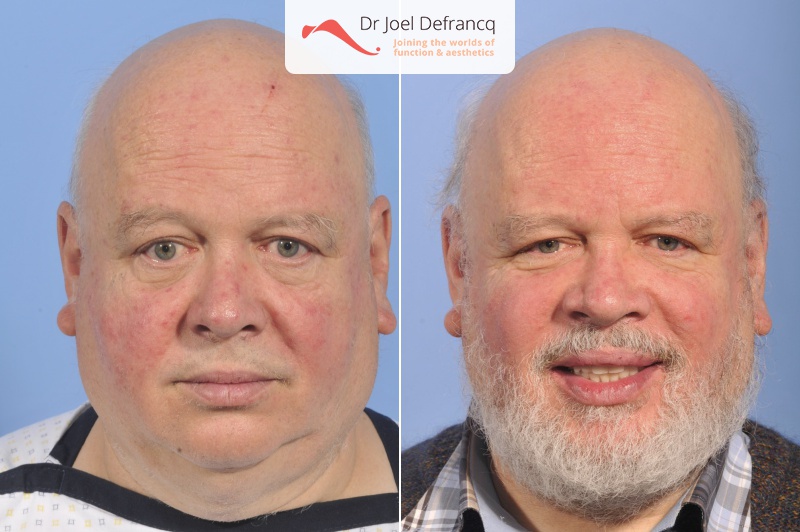

Kaakchirurgie

- Verlenging onderkaak (BSSO)

- Verlenging bovenkaak (Le Fort I)

- Bimaxillary 8-10 mm advancement